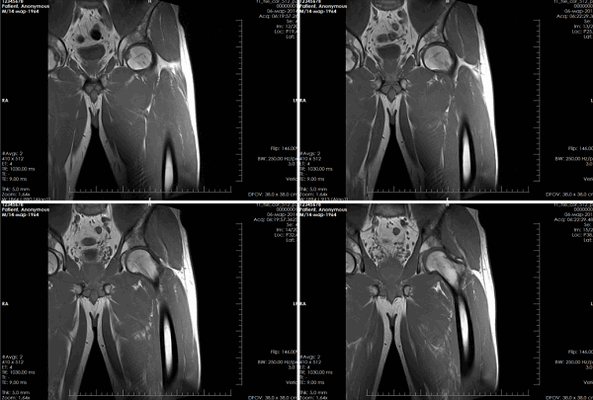

Рисунки 1,2. МР-картина артроза тазобедренных суставов с наличием отека костного мозга дистрофического характера в верхне-наружных отделах вертлужной впадины справа